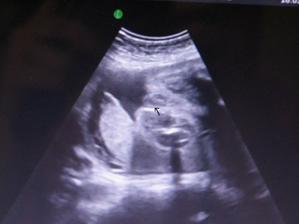

27.1. proběhl velký UTZ, který dopadl na jedničku, mimi měří 22 cm a maminka přibrala od minula 1kg, takže už máme pouze -2kg z počáteční váhy, jsem zvědavá, jak rychle to teď poletí...🙂 a hlavně čekáme maminky vytouženou holčičku...🙂 tatínek je taky rád, jen se těšil na chlapečka////////

17.2. kontrola na 1 🙂 pan doktor byl s námi moc spokojený, zase jsme vyrostli na 26cm a maminka přibrala od minula 2kg, takže jsme na počáteční váze...🙂 další kontrola i s 3D UTZ bude 10.3.2009...:-) Už se těším, až tu naší malou princeznu zase uvidím///////

10.3.09 kontrola dopadla skvěle, až na ten 3d UTZ, ten se nepovedl, 18.3. jdeme znova, tak snad to bude lepší. Malá je u maminky spokojená a stále se vrtí a hýbe, přibraly jsme 1kg, takže všechno v normálu. Další kontrola 31.3.////// Tak kontrola dne 31.3. proběhla v naprostém pořádku, malá je zdravé miminko, maminka přibrala od minula 1,3kg takže nádherná pohoda, obdržely jsme velkou pochvalu od pana doktora 🙂 Malá nám krásně roste, takže podle UTZ jsme starší, termín by nám vycházel na 7.6., místo na 15.6., tak jsme zvědaví, kdy na svět vykoukne. Další kontrola 14.4., už budeme docházet po 14 dnech. Jinak Emmička už je hlavou dolů a okopává mamince žebra, tak uvidíme, jestli už jí to zůstane 🙂/////// Tak další kontrola 14.4. proběhla v naprostém pořádku, malá je stále hlavičkou dolů a maminka přibrala další 1,5kg, opět s pochvalou od pana doktora, takže si neztěžujeme 🙂, další kontrola 28.4. a začneme vyřizovat mateřskou, jupí 🙂/////////takže kontrola v pořádku, váha zase ukazuje o 1,3kg více, všechno se zdá být v pořádku 🙂 Další kontrola 12.5.//////4.5. dnes nám začíná MD 🙂//////